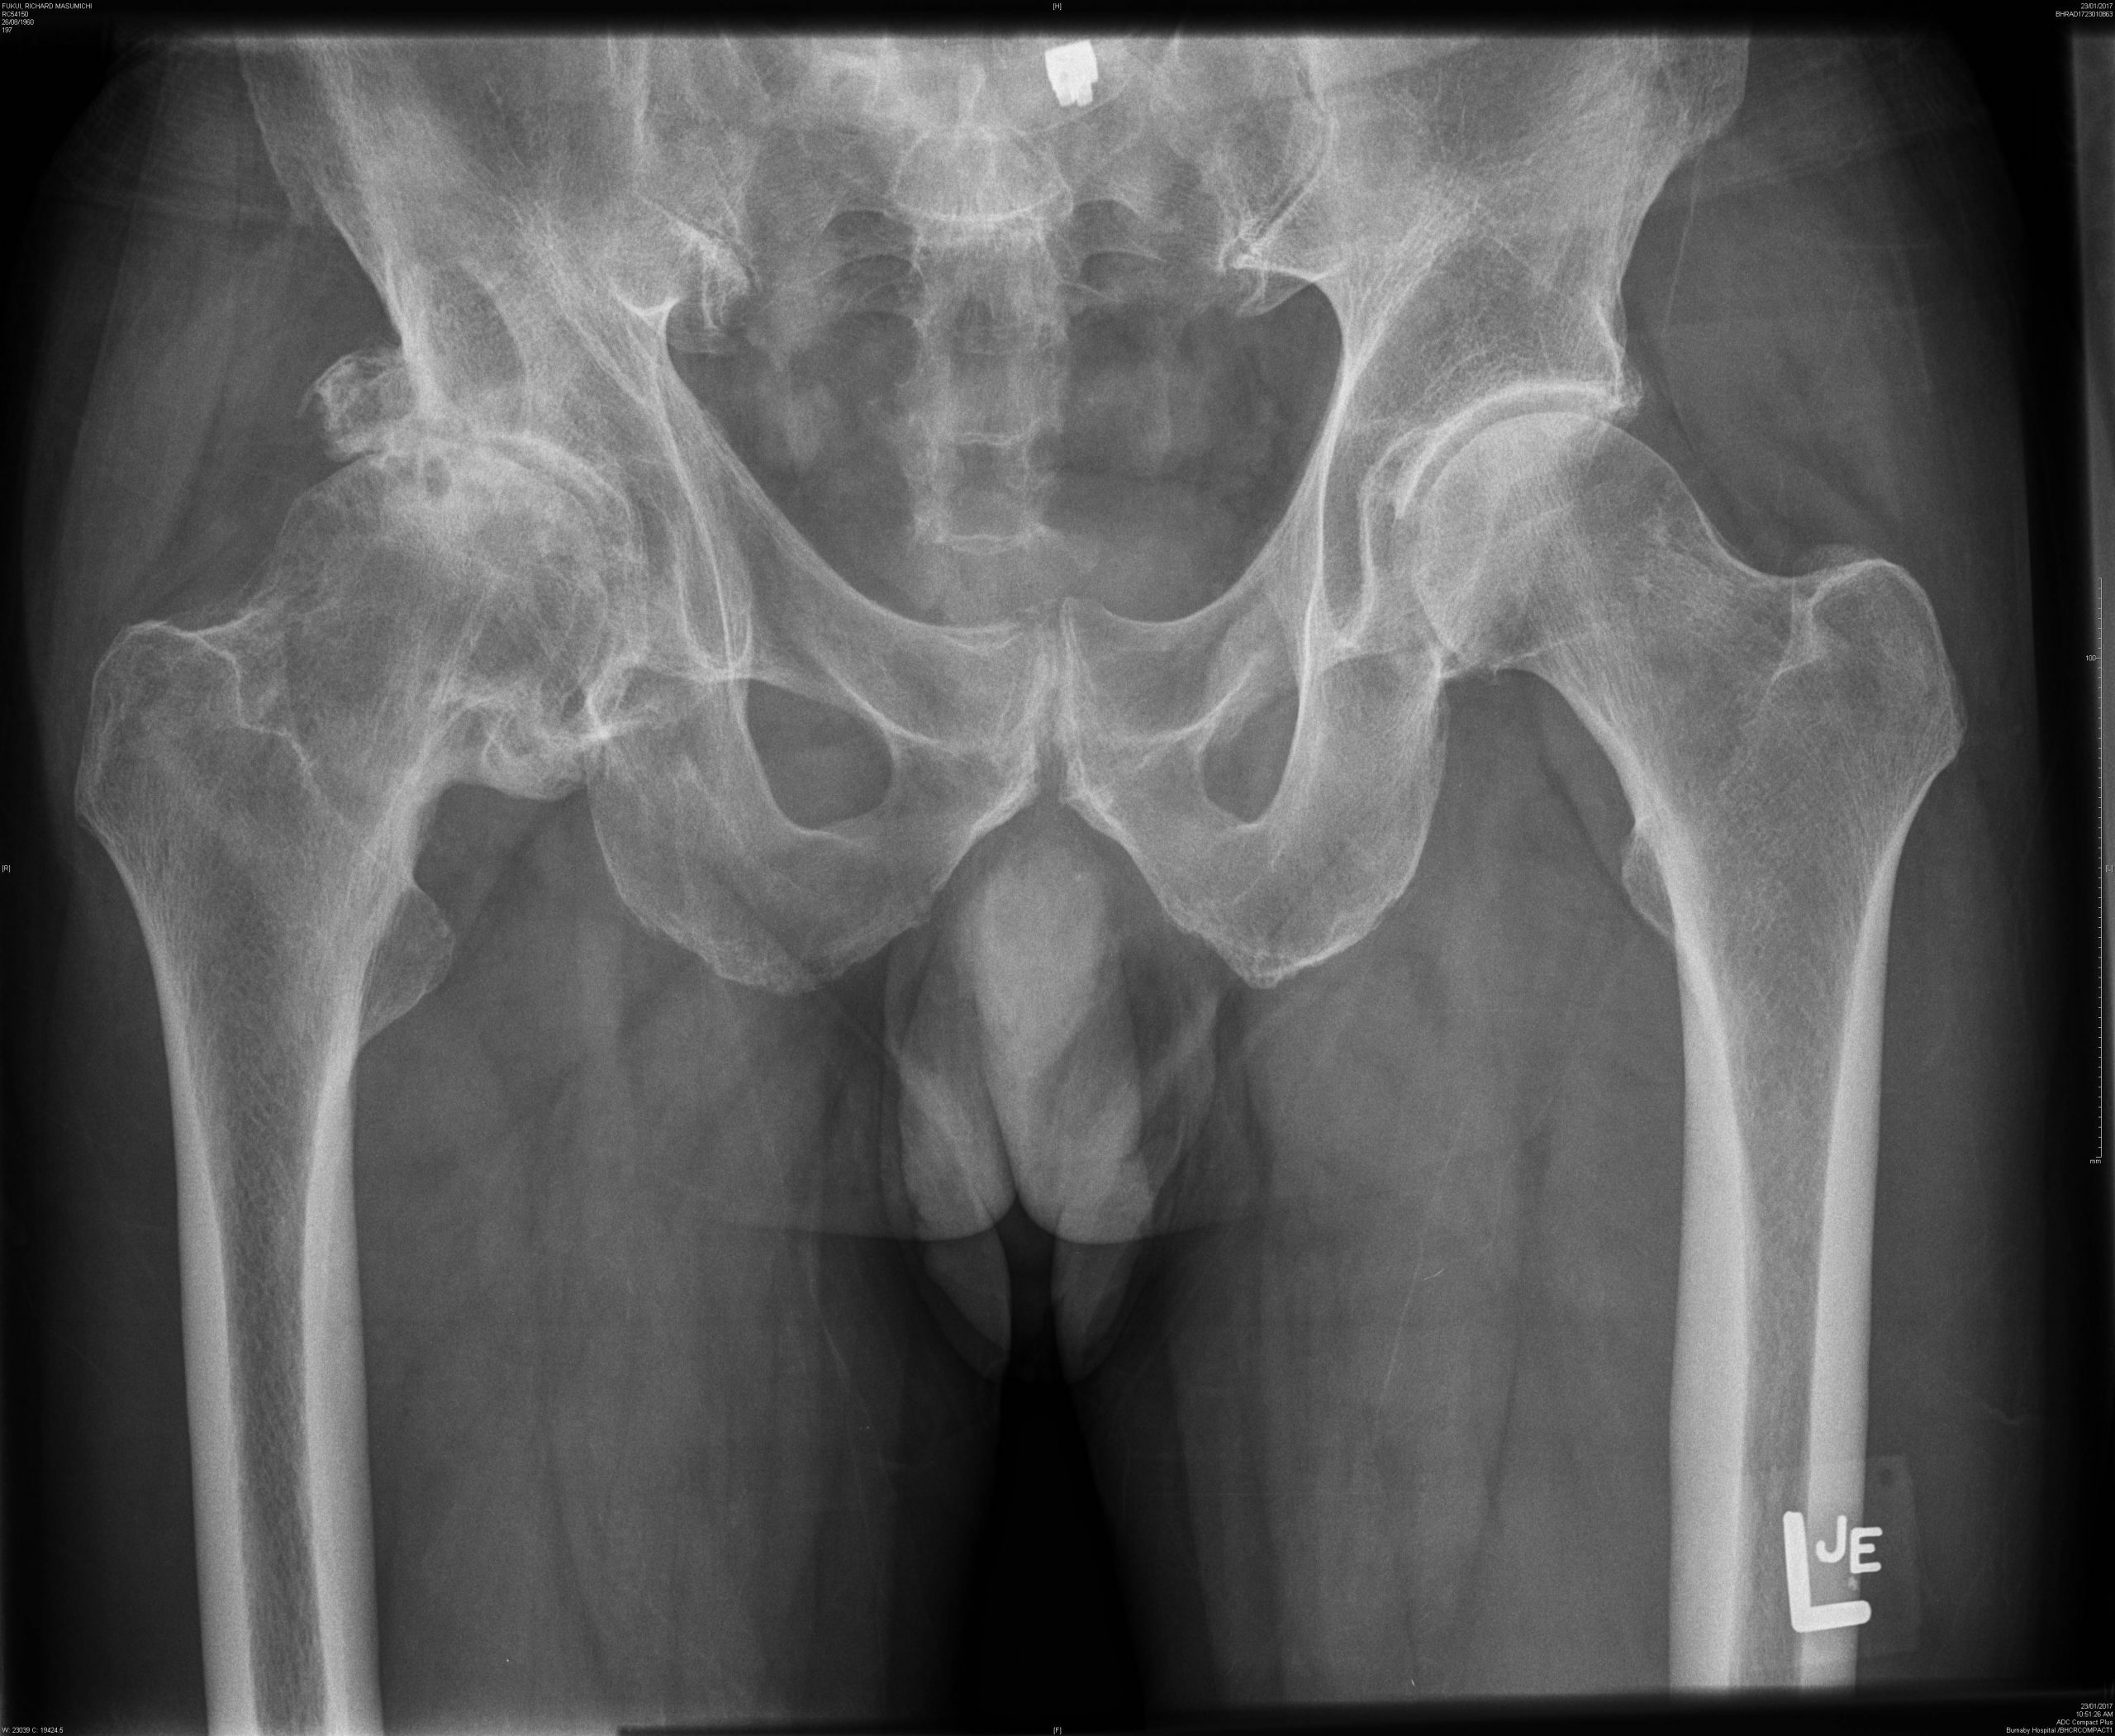

Nonsurgical options for management of hip osteoarthritis An Manual Therapy For Hip Oa To 1) determine if specific dosing parameters of manual therapy are related to improved pain, disability, and quality of life. Manual therapy is one therapeutic approach to treating hoa. The aim of this systematic review was to determine if manual therapy improves pain and/or physical function in people with hip or knee oa. A clinicians should use manual therapy for. Manual Therapy For Hip Oa.